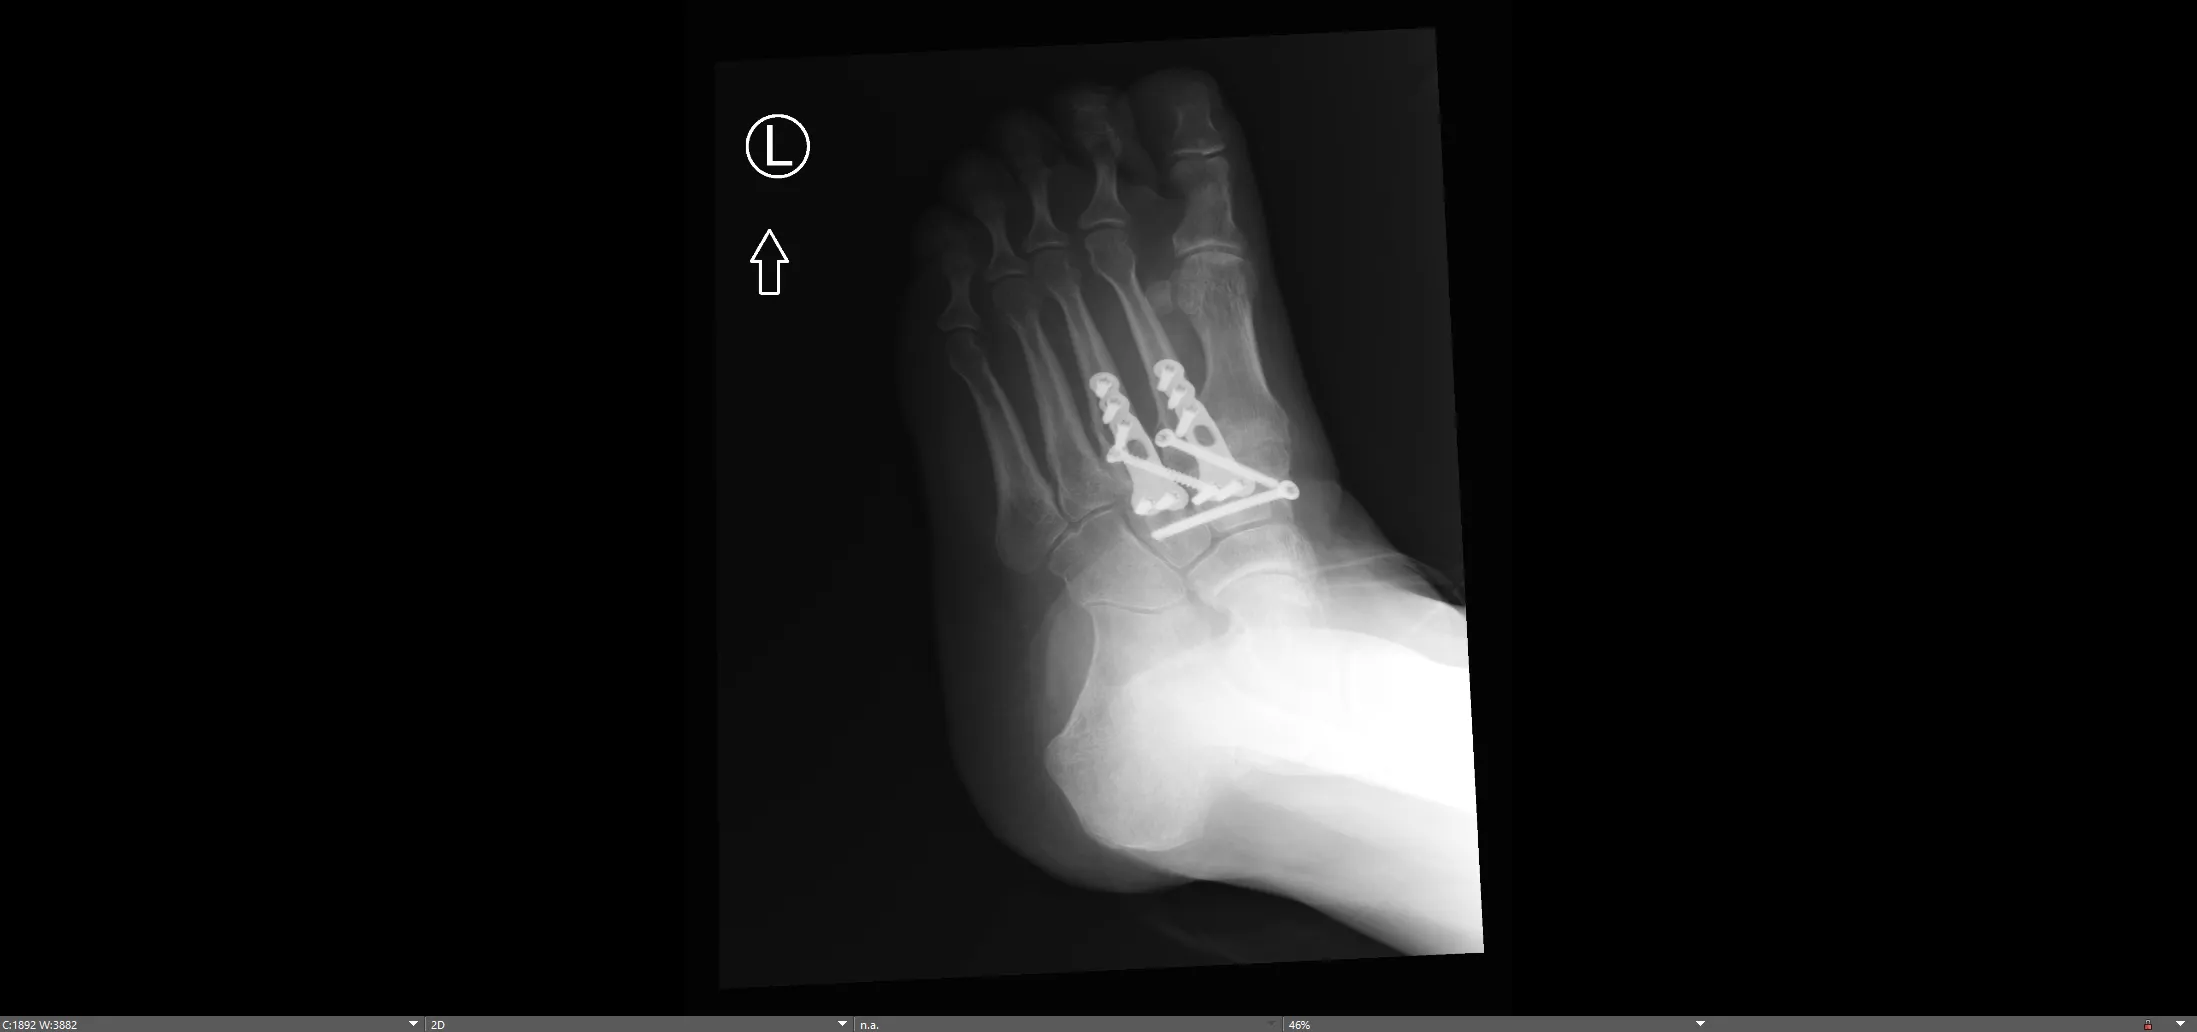

Lisfranc Midfoot Plating System

Multi-hole, low-profile bridging plates specifically designed to span the tarsometatarsal joints for Lisfranc injuries.